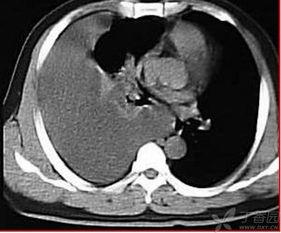

你知道吗?胸部叩诊其实是一种物理诊断方法。当医生用手指敲击胸部时,会产生一种声音,这种声音的音调、音量和音色可以反映出肺部和胸腔内部的健康状况。

- 音调:如果肺部有炎症或者积水,敲击时会产生低沉的音调。

- 音量:如果肺部有空洞或者气胸,敲击时声音会比较大。

- 音色:如果肺部有纤维化或者肿瘤,敲击时声音会变得粗糙。

胸部叩诊的部位主要包括肺部、心脏、胸膜等。医生会根据病情的需要,选择不同的部位进行叩诊。